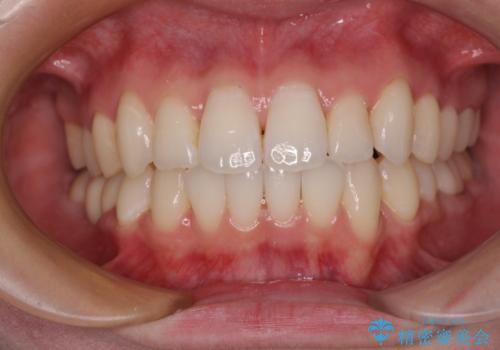

ワーキングホリデー前にきれいな歯列に

- 2、3年後にワーキングホリデーで海外に行くため、その前に歯列やむし歯をきれいにしたいとのことで来院された患者様です。

抜歯の必要な右上の奥歯は事前に抜歯をし、インビザラインにて上下歯列を整えることとしました。

矯正治療後半に奥歯の補綴治療が必要な歯にはオールセラミッククラウンを装着し、インビザラインで最終的に仕上げることとしました。

海外に行く前に口腔内環境を整えることができ、患者様には大変満足していただきました。